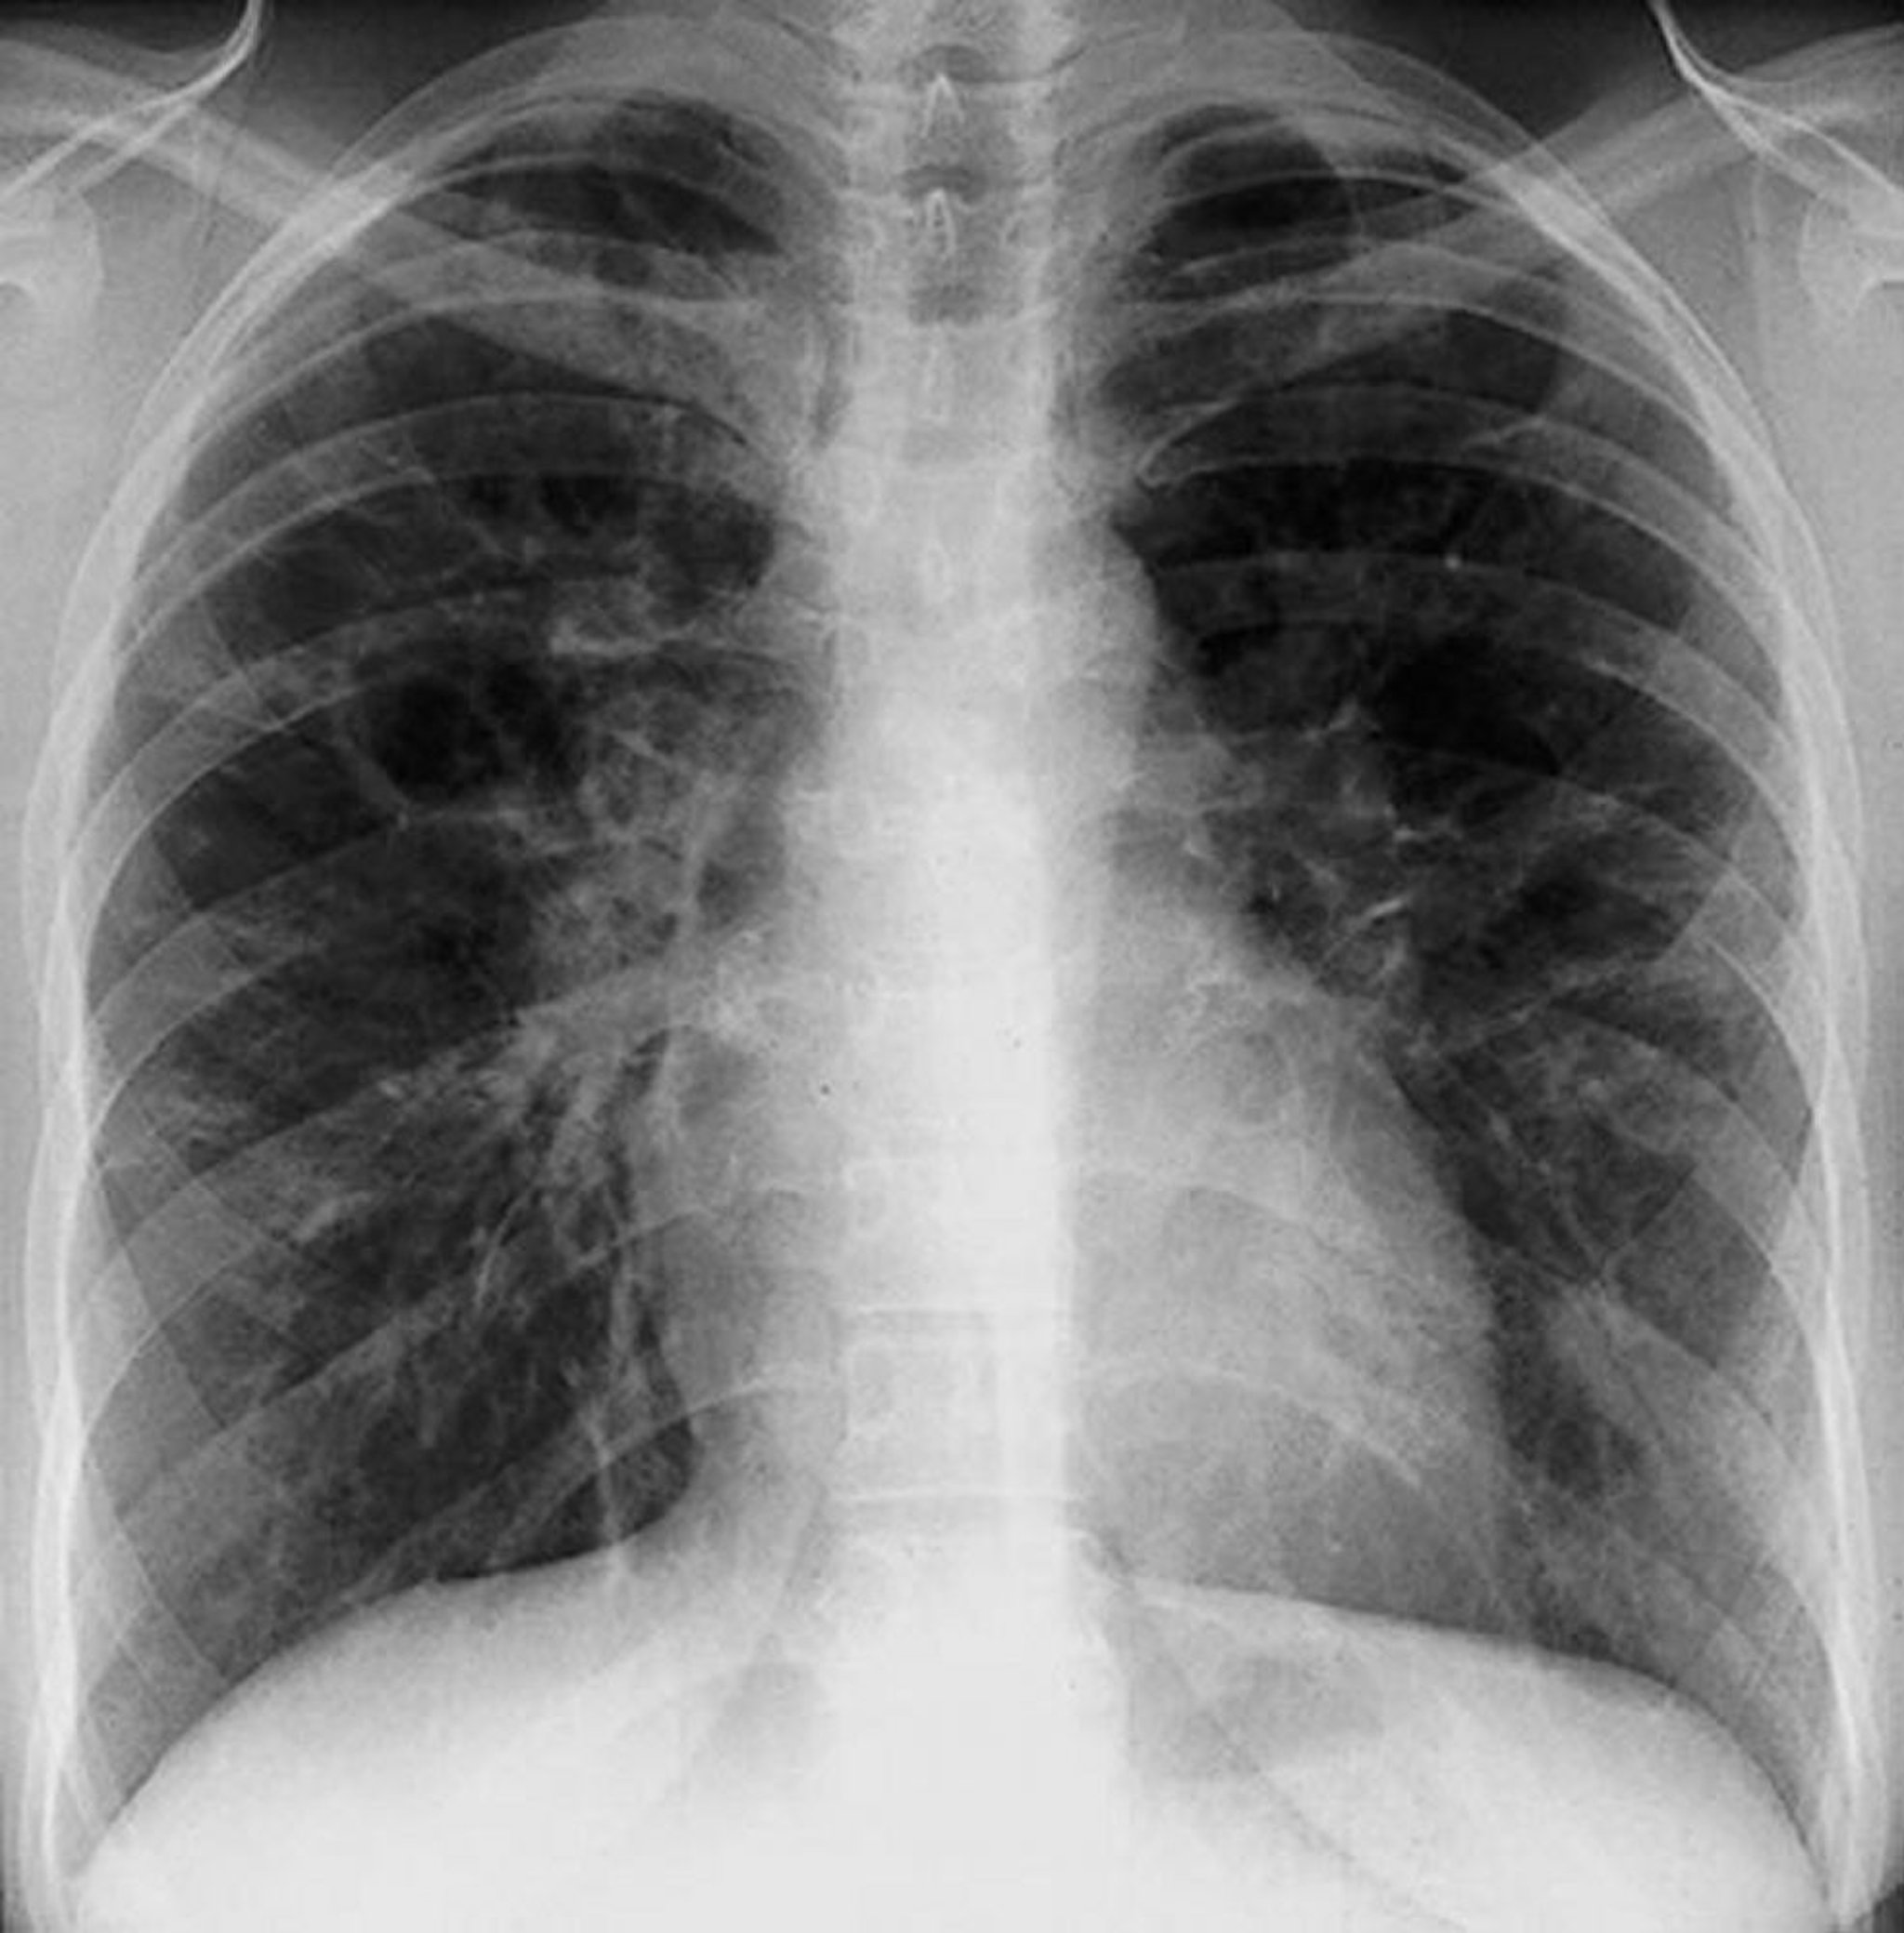

Sarcoidosis (estadio III)

Opacidades intersticiales difusas sin adenopatía hiliar en un estadio III de la sarcoidosis.

By permission of the publisher. De Tanoue L, Elias J. In Bone's Atlas of Pulmonary and Critical Care Medicine. Edited by J Crapo. Philadelphia, Current Medicine, 2005.